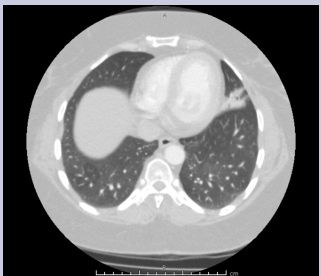

Diagnostic work up showed white blood cell count 7.3, hemoglobin 11.8, platelets 210, and erythrocyte sedimentation rate 30. AFB sputum was negative; legionella urine antigen was negative, blood cultures were negative, INR was 0.9. Non-contrast transthoracic echocardiogram was normal. There was no evidence of shunt on the two-dimensional transthoracic echocardiogram bubble study. Computed tomography of the chest revealed focal opacity in the inferior segment of the lingula [Figure 1 & 2].

Figure 2: CT Thorax showing a focal opacity involving the left lingula